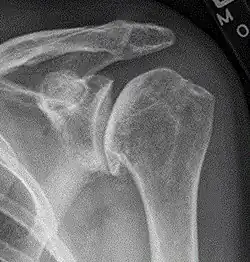

X-ray of shoulder osteoarthritis.

Arthritis of the shoulder causes pain and loss of motion and use of the shoulder. X-rays of the shoulder show loss of the normal space between the ball and socket. X-ray can provide radiographic staging of shoulder osteoarthritis.